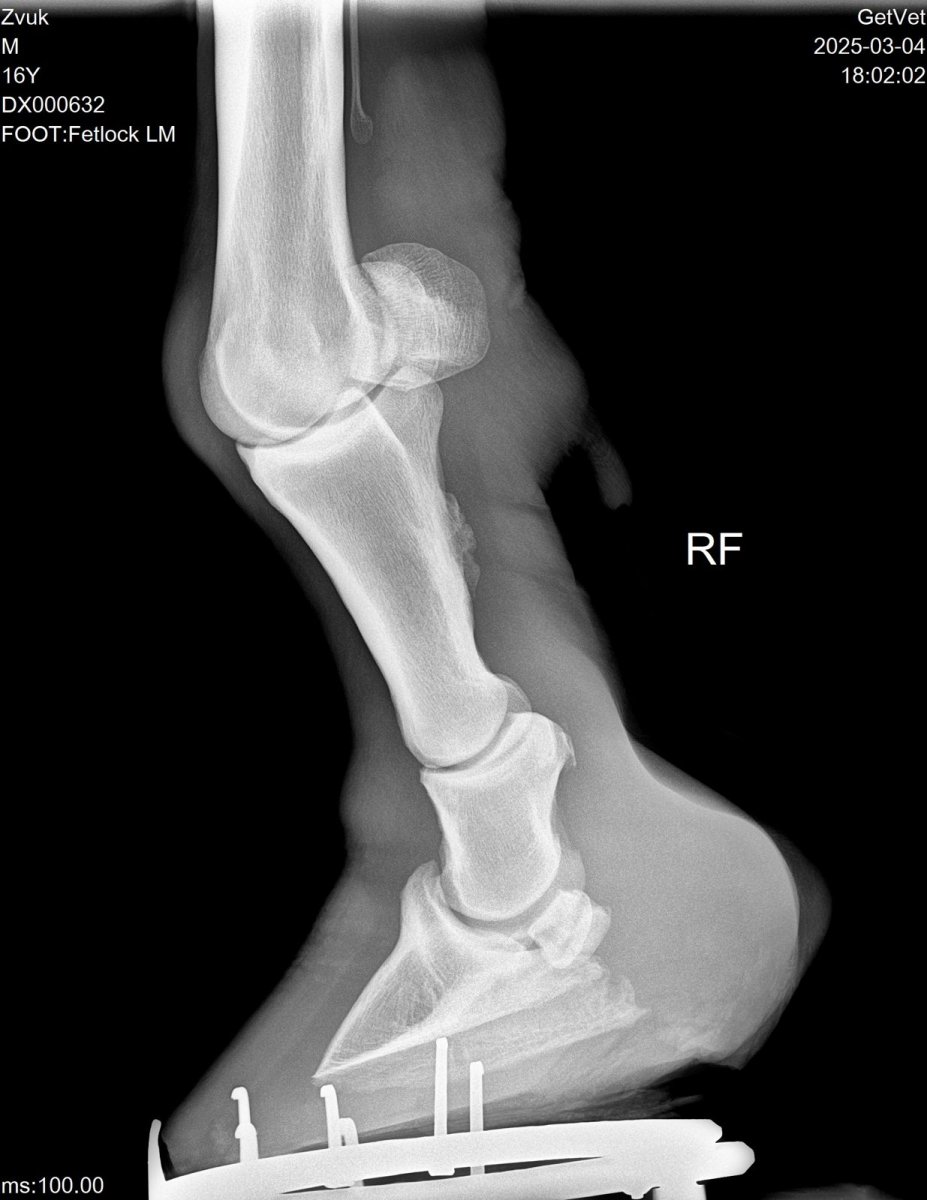

Лошадь, мерин, 16 лет.

10 лет мучается с артрозом путового сустава передней конечности. Еще в то время ветеринар посоветовал колоть Бонхарен. И все 10 лет каждый год вакцина Бонхарен хорошо помогала, и лошадь на какое то время хромать переставала(обычно год или полтора). Однако последнее время Бонхарен перестал помогать и лошадь захромала вновь. Вызвали другого ветеринара, сделали рентген - контрактура сухожилия передней конечности. Сказали однозначно ложить на стол. Операция стоит около 200к, это не считая коневоза туда и обратно, это мы конечно не потянем. Никакие хондропротекторы не помогут. Сказал можно попробовать что то из ортопедии, однако в нашем городе ковалей нет совсем, а из большого города ради одной лошади ортопедический коваль приезжать не станет. Может быть кто то уже сталкивался с такой проблемой. Может можно поколоть другие вакцины, помощнее, что бы хоть как то облегчить ходьбу лошади?